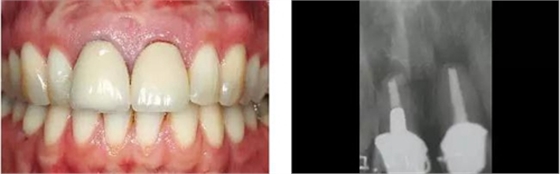

圖11、穿黏膜愈合1周后,牙齦外形良好。

圖12、種植體植入后2個月取出愈合帽,可見牙齦外形和齦乳頭維持得相當好。

圖13、安放全瓷基臺。

圖14、最終修復體就位,冠頸部較窄。沒有任何牙齦和牙齦乳頭的退縮。

圖15、種植體植入后12個月的微笑相。